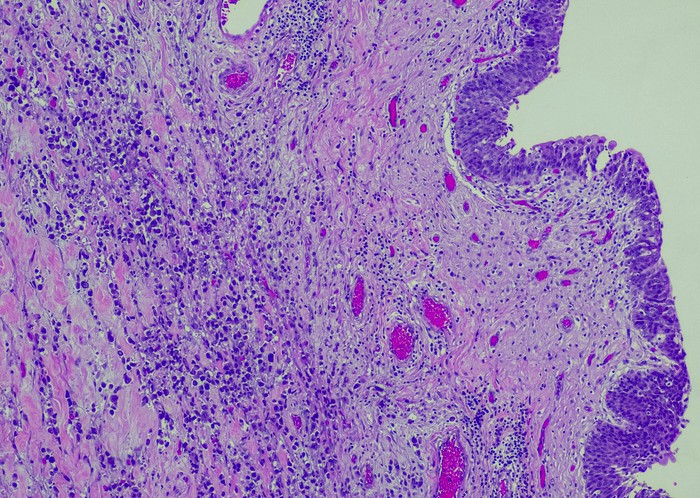

Featured photo at top of urothelial carcinoma cells stained purple. Photo/OGPhoto/iStock.

The research, published in the journal Urologic Oncology, focused on metastatic urothelial carcinoma (mUC), cancer that begins in the urothelial cells, which line the urethra, bladder, ureters and some other organs. Martini, University of Cincinnati Cancer Center physician-researcher and assistant professor in the Department of Urology in UC's College of Medicine, served as corresponding author of the study.